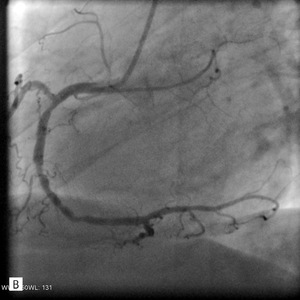

W koronarografii odnotowano następujące wyniki: pień LTW bez zwężeń, gałąź przednia zstępująca – po odejściu gałęzi diagonalnej (D1) subtotalne zamknięcie, na obwodzie istotne zwężenie, D1 – w ujściu zwężenie krytyczne; gałąź okalająca – dwa istotne zwężenia w odcinku początkowym i środkowym, prawa tętnica wieńcowa – dwa istotne zwężenia w segmencie 2 i 3 (ryc. 3).

Rycina 3. Badanie tętnic wieńcowych metodą koronarografii. A. Pień LTW – bez zwężeń, gałąź przednia zstępująca (GPZ) – po oddaniu gałęzi diagonalnej subtotalne zamknięcie, na obwodzie istotne zwężenie. B. Prawa tętnica wieńcowa – dwa istotne zwężenia w segmencie 2 i 3.